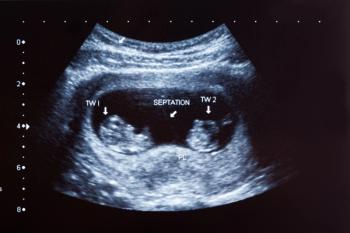

New research reveals that twin fetuses have reduced fat and muscle mass compared to singletons as early as 15 weeks of gestation, offering fresh insight for prenatal care.